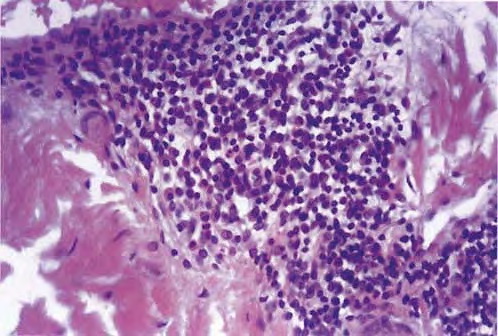

Systemic plasmacytosis = داء كثرة المصوريات الجهازي